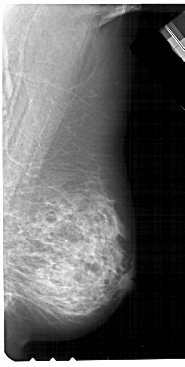

A_1211_1.LEFT_CC

LEFT_CC LINES 5356 PIXELS_PER_LINE 2971 BITS_PER_PIXEL 12 RESOLUTION 43.5 OVERLAY

FILE: A_1211_1.LEFT_CC.OVERLAY

TOTAL_ABNORMALITIES 1

ABNORMALITY 1

LESION_TYPE MASS SHAPE IRREGULAR MARGINS SPICULATED

ASSESSMENT 5

SUBTLETY 5

PATHOLOGY MALIGNANT

TOTAL_OUTLINES 2

BOUNDARY

CORE